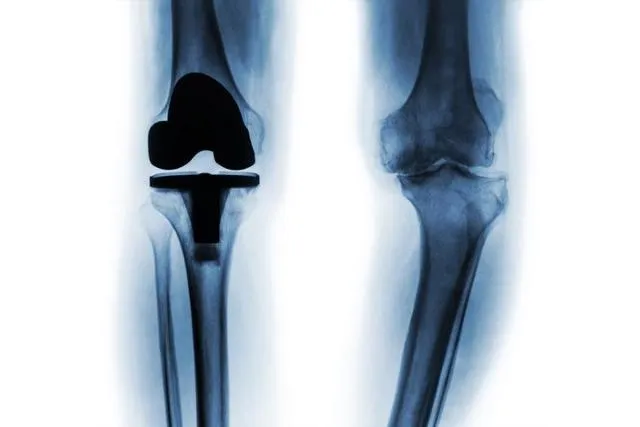

무릎 인공관절 전치환술을 받은 환자들이 수술 후 6개월 이내에 건강 상태가 크게 호전되며, 이 효과가 15년이 지나도 유지된다는 연구 결과가 발표됐다.

최병선·노두현·한혁수 서울대병원 정형외과 교수 연구팀은 2005~2013년 수술을 받은 50대 이상 환자 1,264명을 대상으로 최장 15년간 추적 관찰했다. 신체 활동 능력은 수술 5년 뒤부터 노화의 영향으로 감소했지만, 사회적 기능 점수는 추적 기간 내내 지속적으로 향상됐다.

이번 연구는 무릎 인공관절 수술의 장기 예후에 대한 근거를 제시했으며, 수술 효과 평가 시 신체 기능 회복뿐 아니라 삶의 질과 사회적 기능까지 함께 고려해야 함을 보여줬다.